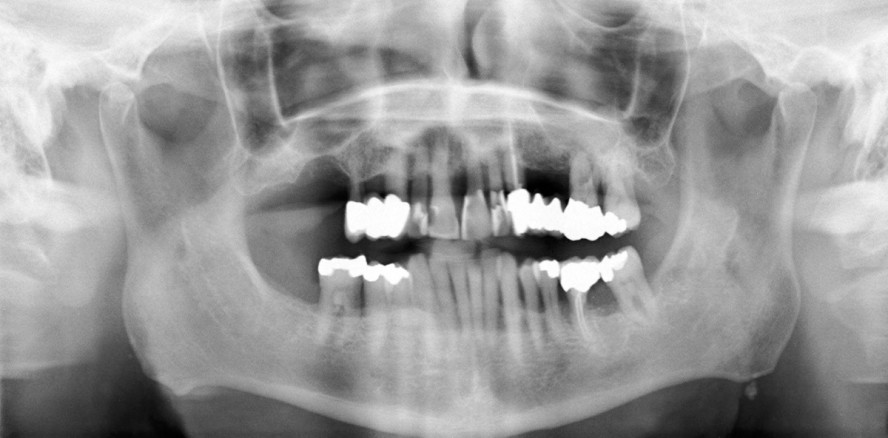

Zusätzliches diagnostisches Hilfsmittel können Röntgenbilder sein. Selbst Bissflügelaufnahmen, die im Zuge einer Kariesdiagnostik bei jungen Patienten von Zeit zu Zeit angefertigt werden, können eine beginnende AgP bereits frühzeitig aufdecken (Cogen et al., 1992; Sjodin et al., 1993). Gerade für eine solch lokalisierte Erkrankungsform, bei welcher häufig die Inzisiven und ersten Molaren zuerst betroffen sind (Lang et al., 1999), sollte grundsätzlich eine Beurteilung des Verlaufs des Limbus alveolaris erfolgen. Neben einer familiären Häufung der Parodontalerkrankung und ein außer der Parodontitis klinisch gesunder Patient gilt insbesondere das rasche Voranschreiten der parodontalen Destruktion als primäres Kennzeichen der AgP (Armitage, 1999; Lang et al., 1999). Diese drei Hauptmerkmale wirken insgesamt leicht beurteilbar, jedoch kann beispielsweise bereits die Definition „schnelle Progression“ Fragen aufwerfen. Fortgeschrittene Destruktionen bei Jugendlichen und jungen Erwachsenen bis 20 Jahre lassen auf eine rasche Progression schließen, wenn man annimmt, dass die Erkrankung in der Pubertät begann. Aber wie bewertet man die Situation bei einem 40-Jährigen? Hat die Destruktion im Alter von 20 Jahren begonnen, so kann man eine langsame Progression annehmen und es handelt sich eher um eine schwere CP. Dagegen könnte die Erkrankung auch erst einige Jahre zuvor begonnen haben und damit sehr rasch verlaufen sein.

Unabhängig von der Diagnose „chronische“ oder „aggressive Parodontitis“ – gute Erfolgsaussichten bestehen bei konsequenter Therapie und Nachsorge für beide Erkrankungsformen. Durch eine lebenslange und individuell angepasste Kontrolle des dentalen Biofilms ist es möglich, den parodontalen Zustand zu stabilisieren bzw. zumindest die Progression der Erkrankung deutlich zu verzögern (Abb. 1 und 2). Somit ist in den meisten Fällen ein Zahnverlust nach Parodontitistherapie unter der Voraussetzung einer regelmäßigen UPT ein eher seltenes Ereignis mit rund 0,1 Zahn/Jahr über einen Untersuchungszeitraum von 10 Jahren (Chambrone et al., 2010; Nibali et al., 2013). Selbst bei Patienten mit fortgeschrittener AgP oder CP werden Überlebensraten der Zähne von 60 bis 97 Prozent innerhalb von einem Jahrzehnt beschrieben (Kamma und Baehni, 2003; Pretzl et al., 2008; Mros und Berglundh, 2010; Bäumer et al., 2011; Graetz et al., 2011). Für jegliche parodontale Behandlungsstrategie gilt jedoch: Je jünger die Patienten und je lokalisierter die Destruktion initial ist, insbesondere bei AgP, umso höher sind die Erfolgsaussichten (Merchant et al., 2014).